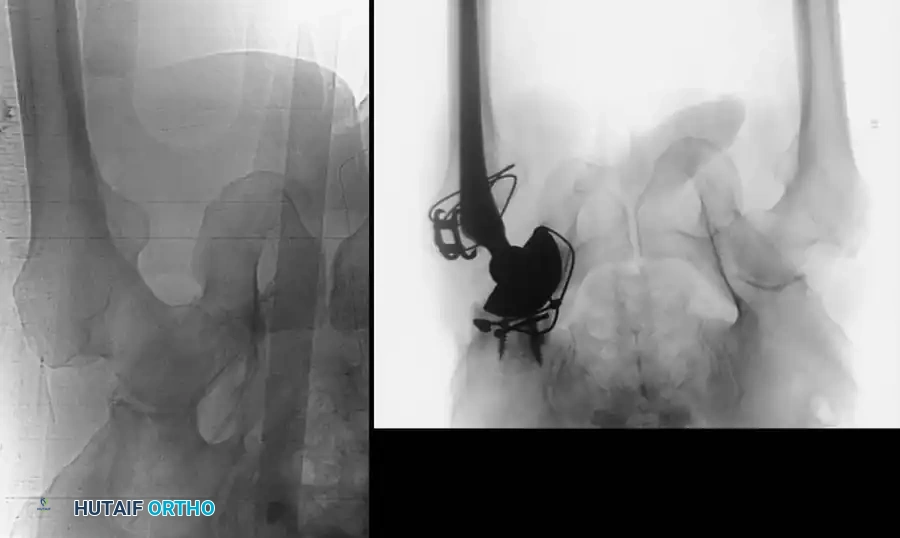

2. Symphyseal Plating (Anterior Ring)

• Positioning: Supine on a radiolucent table.

• Reduction: A Weber clamp or specialized pelvic reduction forceps are placed on the pubic tubercles or via drill holes in the superior rami to reduce the diastasis.

• Fixation: A multi-hole, stout pelvic reconstruction plate (typically 4 to 6 holes) is placed superiorly. Screws must be directed carefully to avoid joint penetration or bladder injury.

The following gallery demonstrates the progression of complex pelvic ring reconstructions, highlighting advanced imaging, intraoperative fluoroscopy, and definitive fixation constructs.

Intraoperative Fluoroscopy and Reduction Techniques